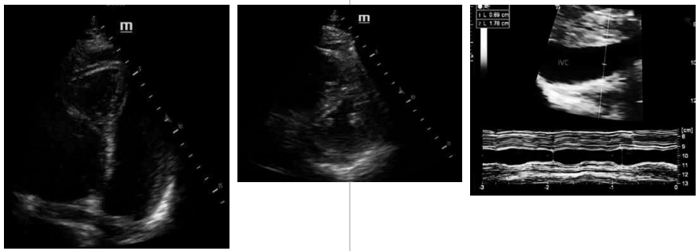

Considerem-se as imagens a seguir.

Ainda com base na situação hipotética apresentada, as imagens indicam a realização de POCUS em uma paciente. Com base nessas imagens, assinale a alternativa correta.